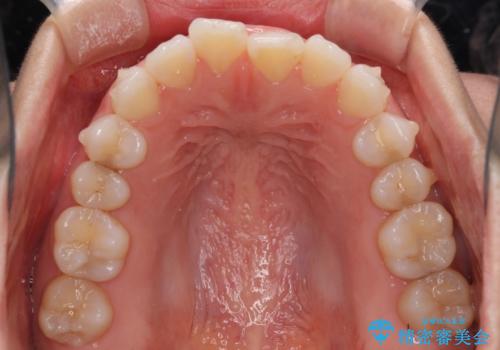

- 上下の前歯の反対咬合を気にして来院された患者様です。

インビザラインを用い、下顎はIPR(歯と歯の間を削る)と歯列全体を後方に移動させ、上顎は前歯を持ち上げることで、反対咬合を改善していくこととしました。

インビザラインによる反対咬合の改善は、上の歯が下の歯を乗り越えていく期間に咬み合わせが非常に不安定となり、治療が長期化することがあります。

こちらの患者様も、一時的に前歯でしか咬めない時期がありましたが、比較的早く咬み合わせが安定し、1年ほどで治療を終えることができました。